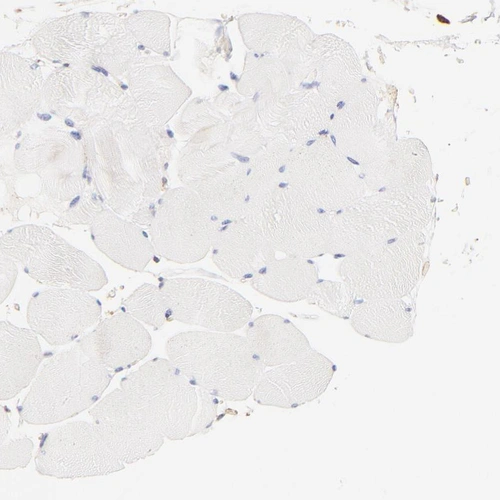

Immunohistochemistry analysis in human prostate and skeletal muscle tissues using HPA002925 antibody. Corresponding FLNA RNA-seq data are presented for the same tissues.